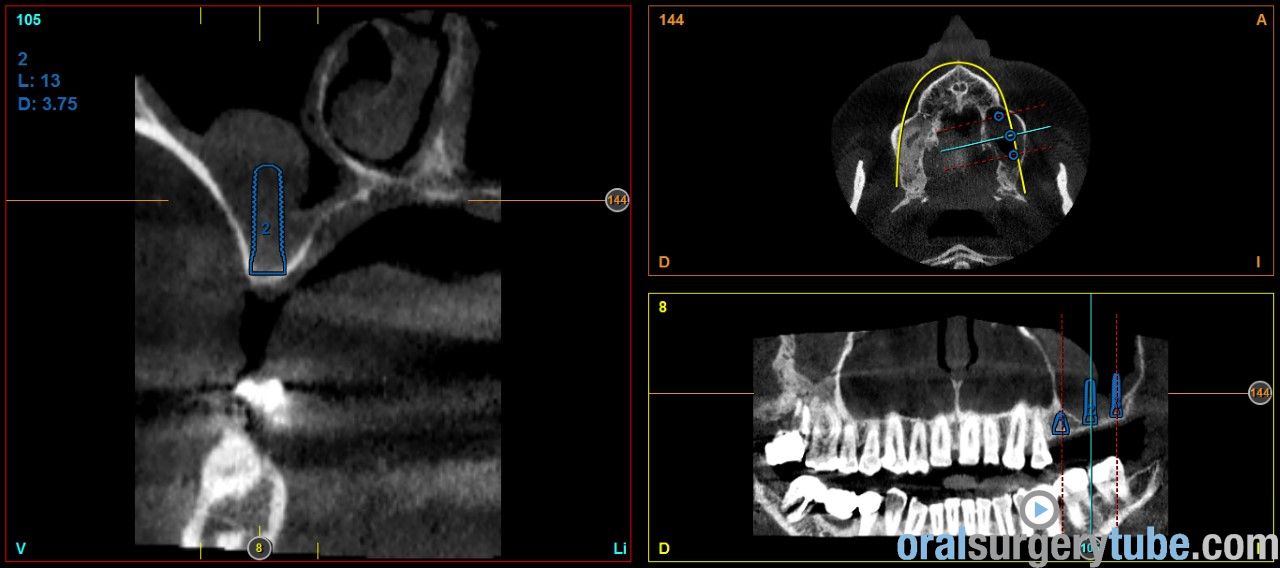

Engrosamiento mucoso

Estimados compañeros, me gustaria saber como abordaríais el seno izquierdo el cual como veis presenta engrosamiento mucoso. Haríais tratamiento previo? Gracias de antemano

Que opináis de dar un corticoide vía oral? Como la dexametasona?. Por cierto repetí el tac después de hacer la elevación derecha y de dar antibiótico y la verdad que el engrosamiento del sebo izquierdo a cambiado más bien poco por no decir que incluso se ha engrosado un poco más, pero eso sí, el paciente no refiere haber tenido en toda su vida síntomas de sinusitis ni alergia, imagino que la causa es la desviación que se ve del tabique hacia la izquierda y la concha bullosa del cornete medio, de verdad no se q hacer, si abordar el seno así ( ya que el paciente no tiene síntomas ) o derivarlo a un otorrino.Tampoco me parece exagerado el engrosamiento, qué opináis?

Hola a todos. Al hilo de este post que he visto, os presento un caso que me ha llegado hace poco a la consulta. Os envío imagenes. Se aprecia engrosamiento de la membrana del seno maxilar izdo. Pensaba darle Trigon Depot 10 días antes de la cirugía y luego valorar. Como lo veis? Muchas gracias.